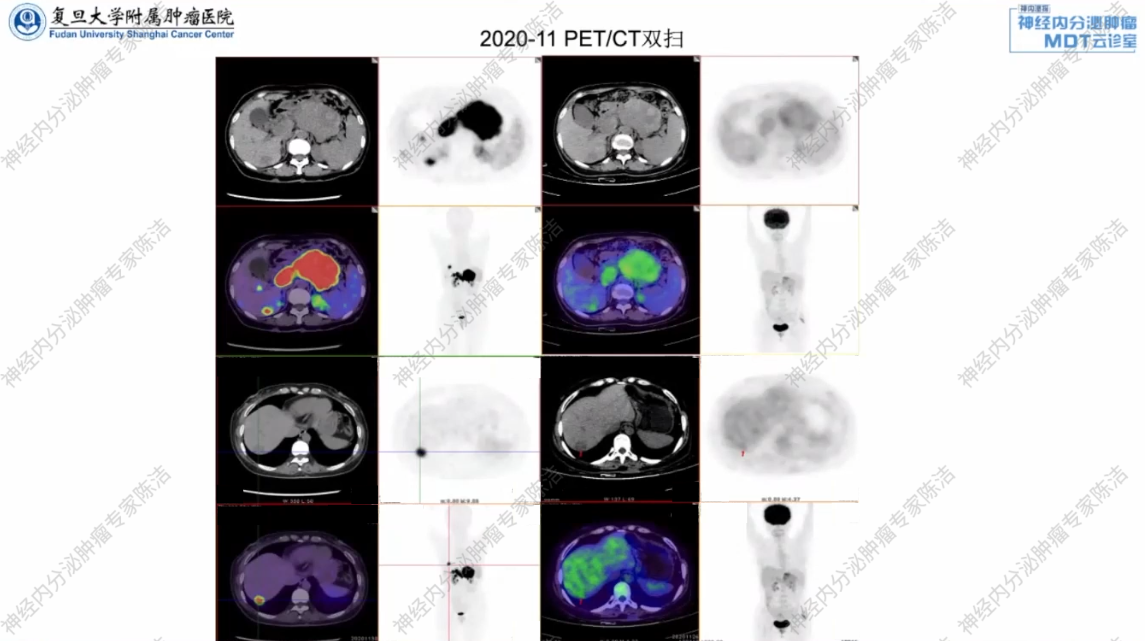

影像学检查:

PET/CT双扫显示,胰尾肿瘤,葡萄糖代谢(FDG)稍活跃,生长抑素受体(SSTR)表达呈强阳性,考虑神经内分泌肿瘤,并门静脉主干及SMV癌栓形成,肝多发转移瘤。

核医学科徐俊彦教授:对于分化良好、Ki-67指数不高的神经内分泌肿瘤(NET G1/G2),其生物学行为通常表现为高表达生长抑素受体(SSTR)而糖代谢(FDG摄取)不活跃。本例患者的PET/CT表现为典型的分化良好NET的特征。这不仅明确了肿瘤的来源,也为后续选择针对SSTR的治疗(如生长抑素类似物或PRRT)提供了分子影像依据。反之,若FDG代谢显著增高,则往往提示肿瘤恶性程度更高、增殖更快,预后也相对更差。